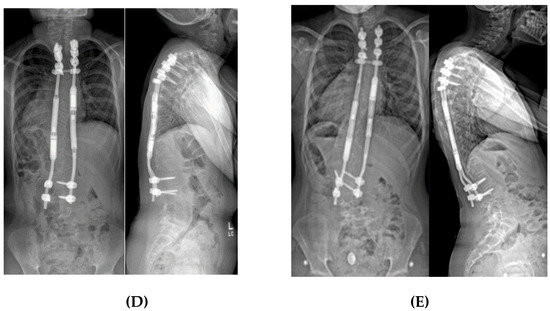

Figure 6.

(A) 10-year-old female with PWS UPD type with 85° kyphosis, a 66° right thoracic and 61° left thoracolumbar curve. (B) Expandable, magnetically actuated rods are implanted from T2–L3, reducing her scoliotic curves to 25° or less, and her kyphosis to 48°. (C) 6 months post-operatively with developing proximal junctional kyphosis. Kyphosis now measures 81°.

Figure 7.

(A) 11-year-old female with PWS UPD type with 70° scoliosis, and 60° kyphosis. (B) Same patient at 12 years of age, after T2–L2 posterior spinal fusion. Overall kyphosis measures 50°. (C) Same patient at 3 years post-operatively with 60° distal junctional kyphosis.

The most common complication affecting outcomes of spinal instrumentation is adding-on of the curve above or below the construct, usually as proximal or distal junctional kyphosis (PJK and DJK, respectively); PJK being the most frequent problem (Figure 6 and Figure 7). Patients with PWS characteristically have a “head forward” posture with their C7 vertebral plumb line falling much farther anterior to the sacrum than would be seen in a typically developed person [11,13]. This occurs by a combination of flattened cervical lordosis and/or thoracic hyperkyphosis. In fact, most PWS curves are kyphoscoliotic rather than the lordoscoloisis seen in idiopathic scoliosis cases. If the sagittal alignment is “anatomically” corrected surgically, patients often will compensate by increasing kyphosis, leading to hypolordosis or even kyphosis in the cervical spine, PJK and DJK [9,41]. In addition, up to 62% of patients with PWS have low bone mineral density and other musculoskeletal manifestations [11,42,43,44,45,46]. The combination of the PJK/DJK and bone weakness leads to a rate of hardware pull out/failure/rod fracture between 17% and 31% [9,40,41,47,48]. The consequences can be catastrophic [49].

In surgical planning, positioning and density of anchoring hardware (primarily pedicle screws) should be chosen with osteoporosis/osteopenia in mind. Thoracic kyphosis should be addressed judiciously – patients with kyphosis or kyphoscoliosis should not have their sagittal profile corrected to values appropriate for typical patients. In most kyphotic deformities, we strive for a resulting kyphosis of 50° to 60°, depending on the initial measurement and sagittal balance. We will select T3 or lower as our upper instrumented vertebra, to allow enough room for the patient to adjust their kyphosis across the cervical-thoracic junction.